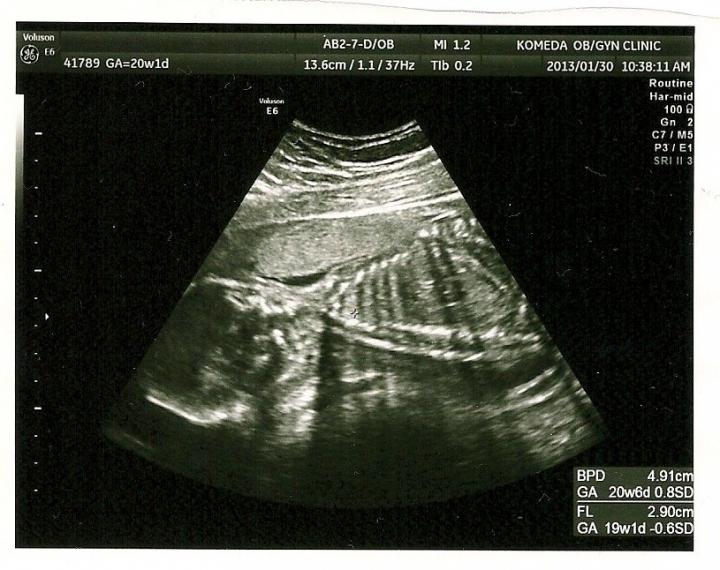

すくすく 大きくなっていました(^^)

性別は まだ わからなかったけど、元気なら いいか☆